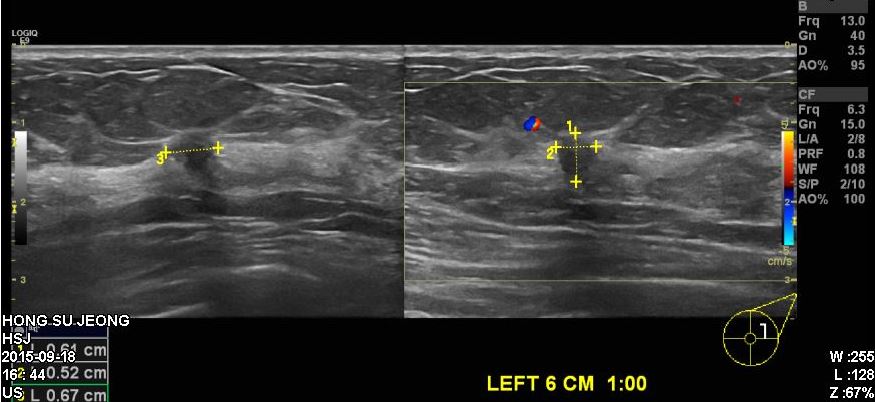

건강검진상 이상소견으로 정밀 검사 위해 내원하신 50대 여성 분으로  좌측 6시방향에서 1cm 떨어진 곳에 의심스러운 혹 조직검사 시행후 좌측 침윤성 유관암 진단 되었습니다.